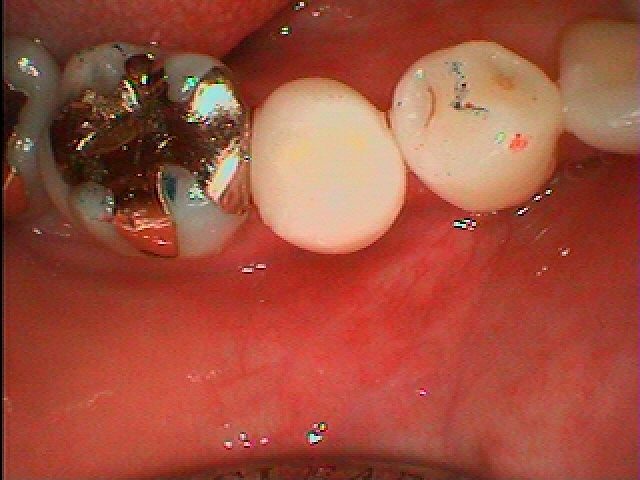

銀歯をすべてセラミックへやり変えていきます セラミックを用いた臨床例 審美治療|お知らせ |広島市安佐南区の歯科医院 銀歯をすべてセラミックへやり変えていきます セラミックを用いた臨床例 審美治療 トップ お知らせ・ブログ お知らせ 銀歯をすべてセラミックへやり変えていきます セラミックを用いた臨床例 審美治療 銀歯をすべてセラミックへやり変えていきます セラミックを用いた臨床例 審美治療 左上の6番部になります この銀歯を外して虫歯治療を行っていきます 中はこのようになっていました 近心部の虫歯を除去していきました CR樹脂にて覆罩を行っています セレックセラミックにて修復しています 銀歯が外れたとのこと わずかに虫歯が存在していました セレックセラミックにて修復しています 綺麗に仕上がりました Web診療予約 初めての方へ 選ばれ続ける理由 院内設備について 歯が痛いしみる一般歯科 歯がぐらぐらする歯周病 健康な歯を保ちたい予防歯科 子供の虫歯予防をしたい小児歯科 銀歯をセラミックに審美歯科 白い歯を目指しませんか?ホワイトニング 矯正専門医がいるので安心矯正歯科 抜けた歯を補いたいインプラント・入れ歯 医院案内 スタッフ紹介 メリィハウス歯科クリニックオフィシャルホームページ ラベンダー歯科クリニックオフィシャルホームページ お知らせ・ブログ ホーム 診療科目 一般歯科 歯周病治療 予防治療 小児歯科 審美治療 ホワイトニング 矯正歯科 入れ歯・インプラント マウスピース矯正 初めての方へ 院長・スタッフ 設備紹介 医院案内・アクセス メニューを閉じる